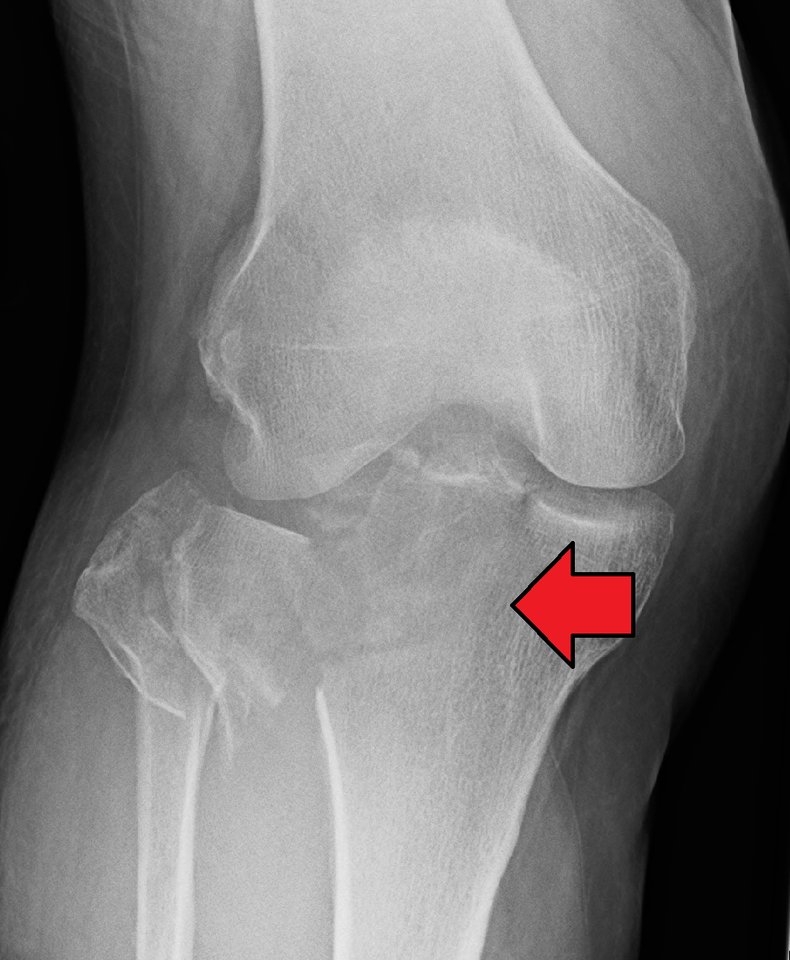

Такое опасное повреждение может внутрисуставным и внесуставным. В свою очередь, внутрисуставные повреждения делятся на открытые и закрытые. Они могут сопровождаться и другими повреждениями в виде разрыва связок, менисков, образования сосудисто-нервных пучков. Обнаружить перелом колена можно по следующей тревожной симптоматике:

- Отёчность околосуставных мягких тканей.

- Деформация суставного элемента.

- Вторичное смещение костей и мыщелковых осколков.